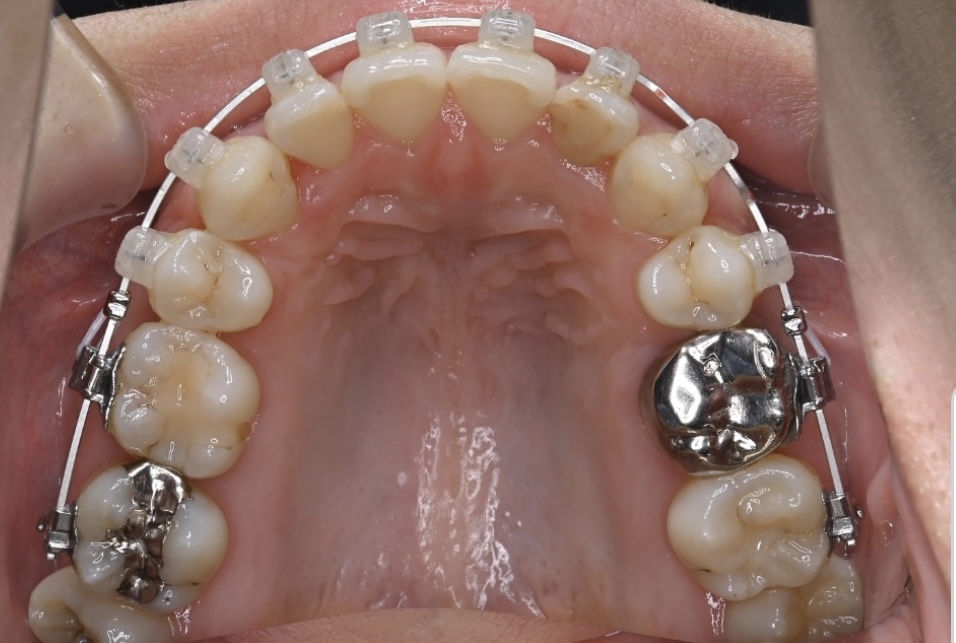

治療経過(1年後)

治療開始からわずか1年で、

✅ 前歯のガタガタがかなり整いました

✅ 前歯の噛み合わせも改善しました

写真で比較すると、その変化は一目瞭然です。

内側を向いていた上の前歯は良い角度になり、下の前歯も正常に近い見え具合となりました。抜いたところの隙間は順調に閉じ、ガタガタもなくなりました。

あとは微調整を数回行い、装置を撤去していく予定となっております。